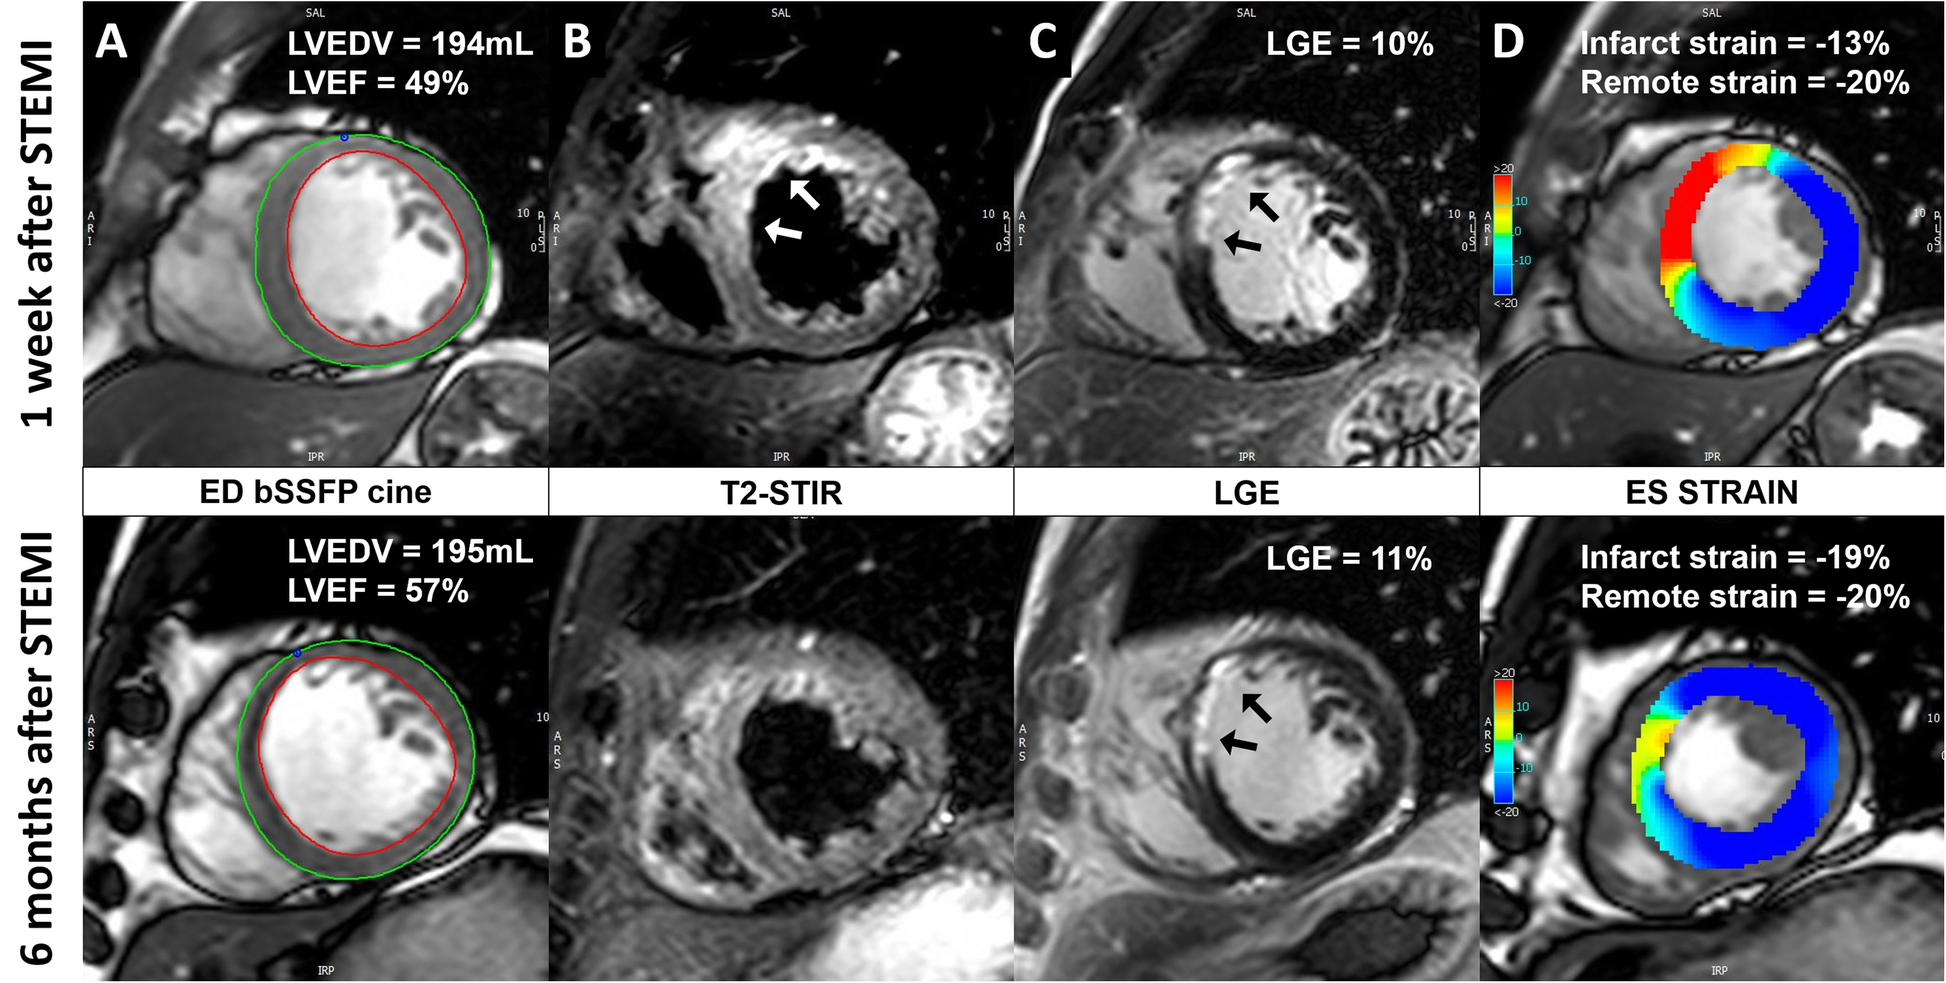

A patient with a mid-LAD infarct receiving early intravenous metoprolol. a, bSSFP end-diastolic images with endo- and epi-cardial contours. The LV volumes remained stable and the LVEF increased at 6 months after STEMI. b, T2-STIR images showing the presence of edema (white arrows) at 1-week after STEMI. c, LGE images showing the presence of acute ischemic injury/infarct scar (black arrows) at 1 week/6-months after STEMI. d, end-systolic bSSFP images with feature-tracking circumferential LV strain overlay. At 6 months the infarct zone circumferential strain improved while the remote zone strain remained stable

The same abbreviations were used as in Fig. 3